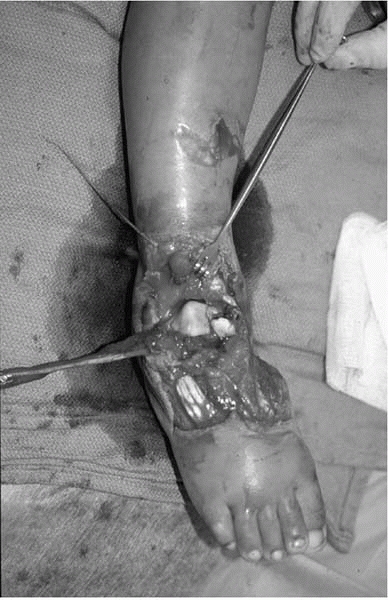

high-energy trauma. The most common areas are the forearm and tibia, or

an open fracture of the foot and ankle when the foot is run over by a

car or school bus (Fig. 4-4). As in adults, the

![]() |

|

▪ FIGURE 4-4

Most open fractures in children are grade 1 open injuries to the forearm or leg. Unfortunately, open ankle and foot injuries are also common in urban areas when young feet are under moving car tires. |